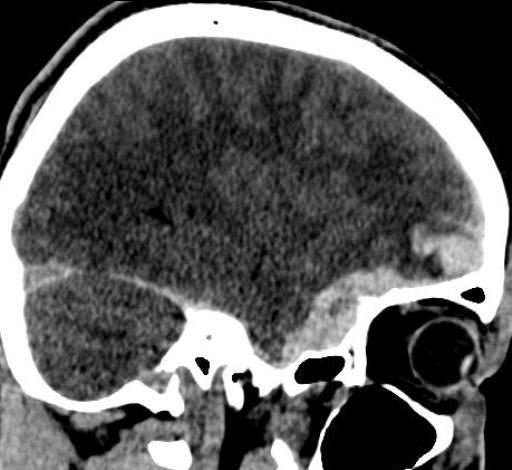

Кт головного мозга, травма.

Молодой человек 24 лет, вчера избит. Поступил в сознании, оринтирован, заторможен несколько.

Уважаемые коллеги, как Вы считаете: помимо всего прочего, имеет ли место субдуральная гематома в передне-медиальном отделе средней черепной ямки справа или это проявление субарахноидального кровоизляиния? Мнения наших экспертов разошлись)). Спасибо!

По моему присутствует контузионный очаг в лобной доле справа, субдуральная гематома и САК.

Заодно и перелом затылочной кости слева.

Когда парня били, он упал и ударился затылком. Кроме линейного перелома затылочной кости слева, других переломов нет, искала очень тщательно.

Спасибо за мнения! Выставила ушибы лобной и височной доли справа, плащевидную субдуральную гематому лобно-теменно-височной области до 3 мм толщиной с переходом на основание черепа, где в передне-медиальном отделе ср.черепной ямки гематома до 10 мм толщиной, + САК; периорбитальные ушибы мягких тканей. Пока нейрохирурги приняли решение вести пациента консервативно.